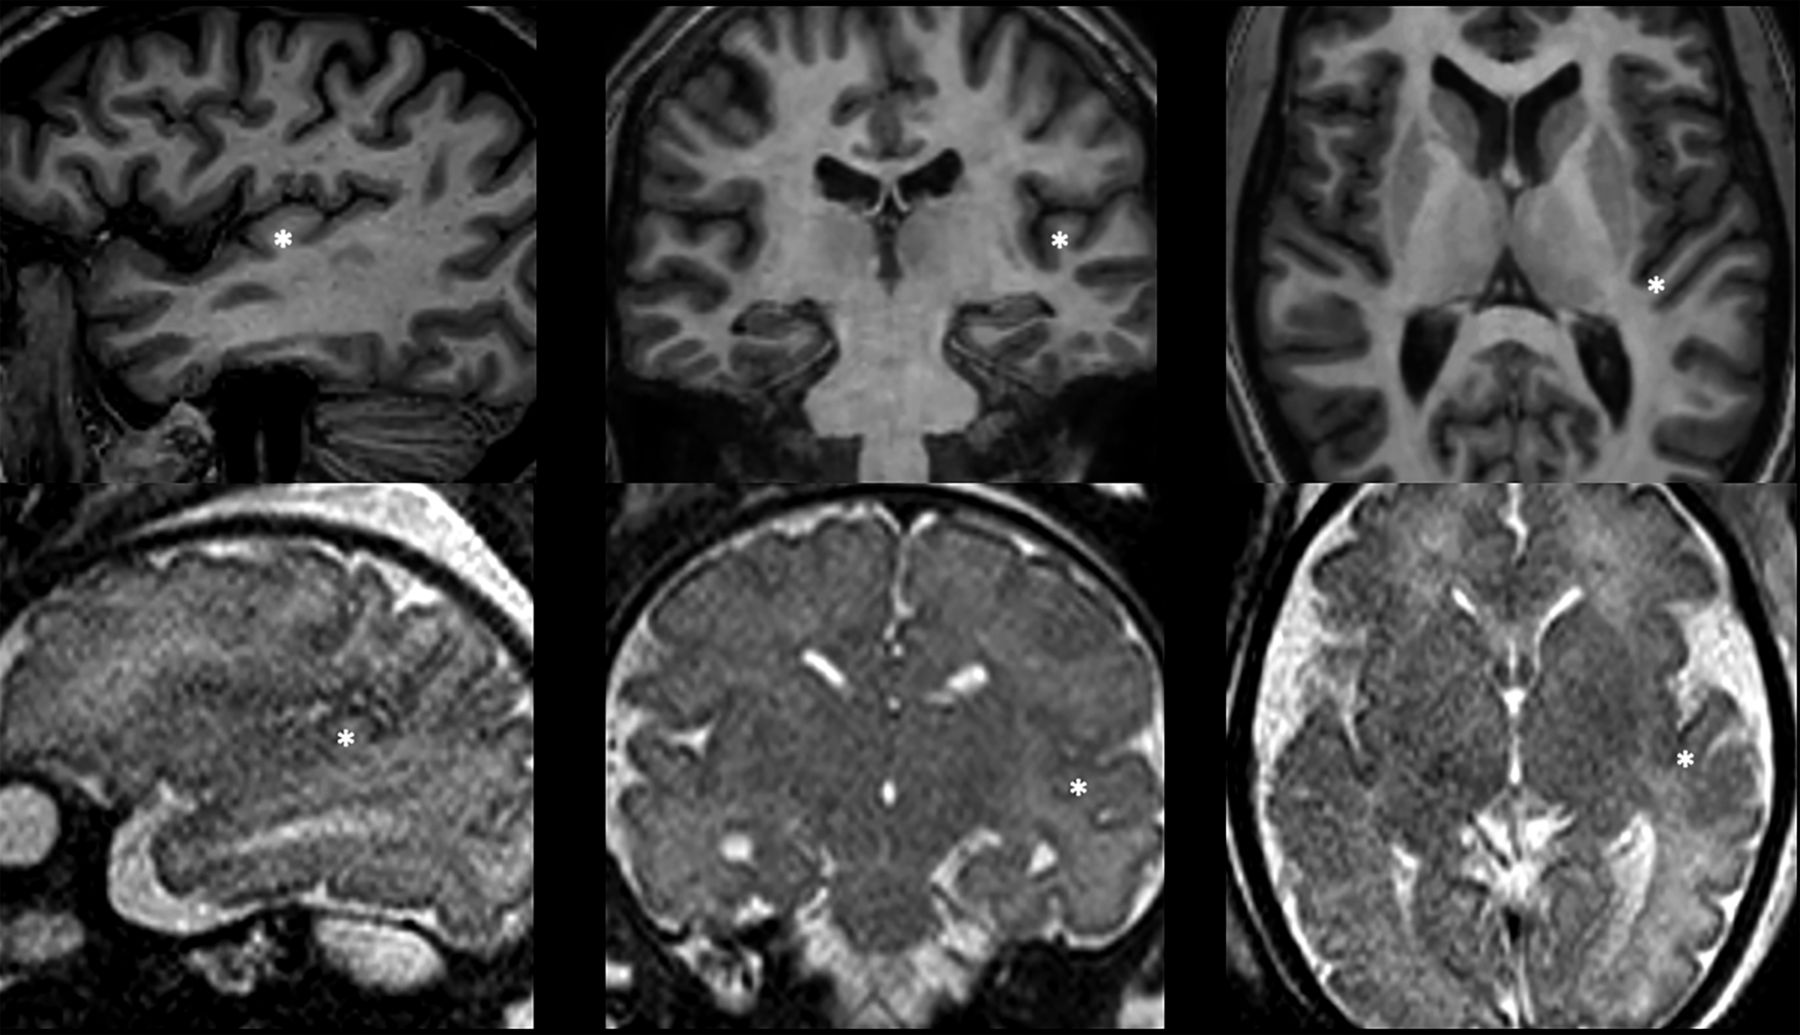

All MR images were analyzed in consensus by 2 neuroradiologists with >5 years' experience in prenatal neuroradiology. Postnatal HG landmarks were used as a reference on T2WI (Fig 1). On axial sections, the HG was visualized on the slice passing through the interthalamic adhesion as an oblique structure of the planum temporale with a posterior-anterior and medial-lateral dislocation.7,16 On sagittal and coronal sections, the HG appears as a protrusion above the posterior part of the superior temporal gyrus (Fig 1).4⇓-6

Representative images of adult (upper row) and fetal (lower row, 28 weeks' GA) HGs on the 3 orthogonal planes. Adult landmarks were used to correctly identify the HG on the fetal brains (asterisk).

The SI of the HG in representative adult (left) and fetal (right, 28 weeks' GA) brains. The characteristic adult heart-shaped configuration in the sagittal plane was used for SI identification on fetal scans.